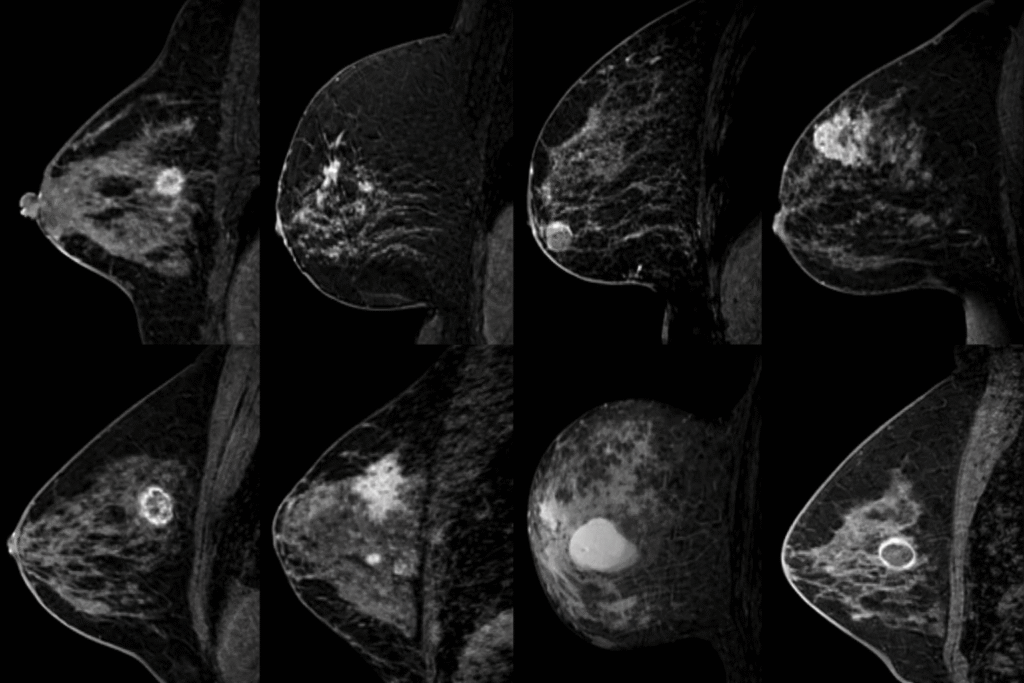

RM de Mamas con Curvas Dinámicas

Evaluación avanzada que analiza el comportamiento vascular de las lesiones en tiempo real, permitiendo una diferenciación precisa entre patologías benignas y malignas con tecnología.